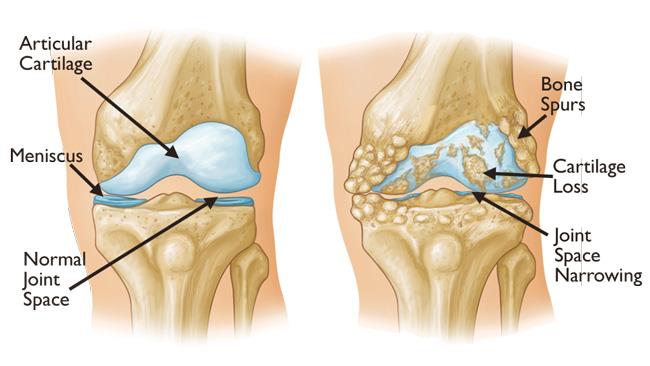

Knee arthritis is known to affect joint functionality causing knee pain and even leading to disability as it progresses. As the cartilage disintegrates, it can cause pain, stiffness, and swelling. The loss of cartilage, the wearing of the bones, and the bony spurs can change the shape of the joint.

As time goes on, the bones will start to rub together, and bone spurs can develop. Stage 2 (mild) stage 3 (moderate) stage 4 (severe) takeaway. Bilateral knee arthritis occurs when both knees are affected with oa.

Learn about the causes, symptoms and treatment. There are different stages of knee osteoarthritis (oa), with 0 assigned to a normal, healthy knee right up to the advanced stage 4, that is severe oa. With oa, the cartilage within a joint begins to break down and the underlying bone begins to change.